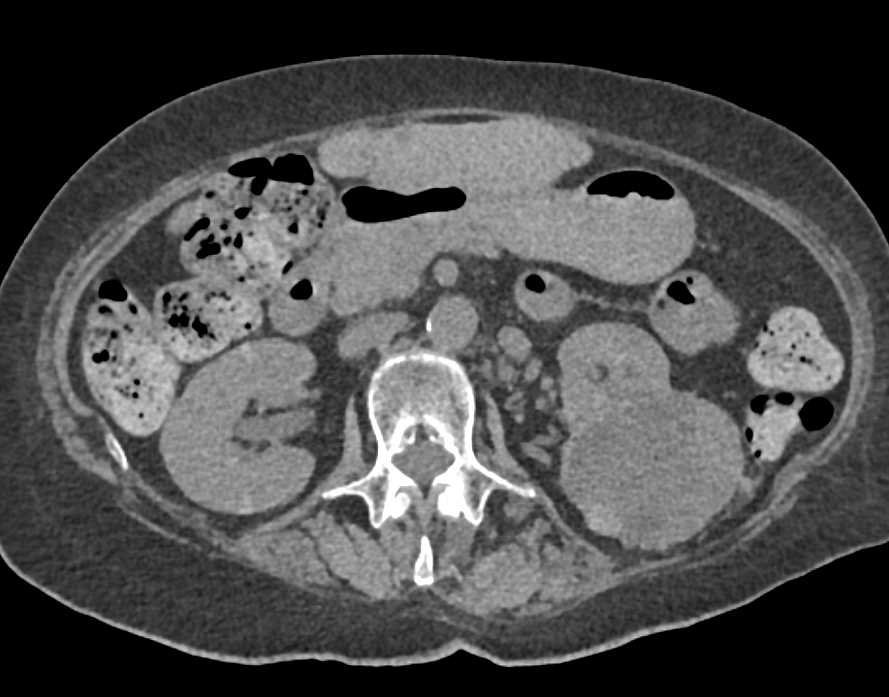

Right Renal Transplant with Vascular Shunting